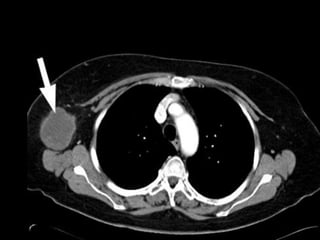

Thorax

Lymphatic Drainage Thoracic

Contents

 3 groups of lymph nodes

 Superior mediastinal lymph nodes

 Posterior mediastinal lymph nodes

 Tracheobronchial lymph nodes

Superior mediastinal

Posterior mediastinal

Tracheobronchial